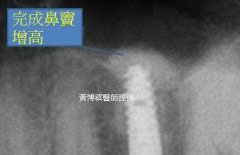

待完成鼻竇增高術後,便可植入適當長度的人工牙根。 |

最後等人工骨粉癒合,作上假牙,回復正常咬合功能。 |